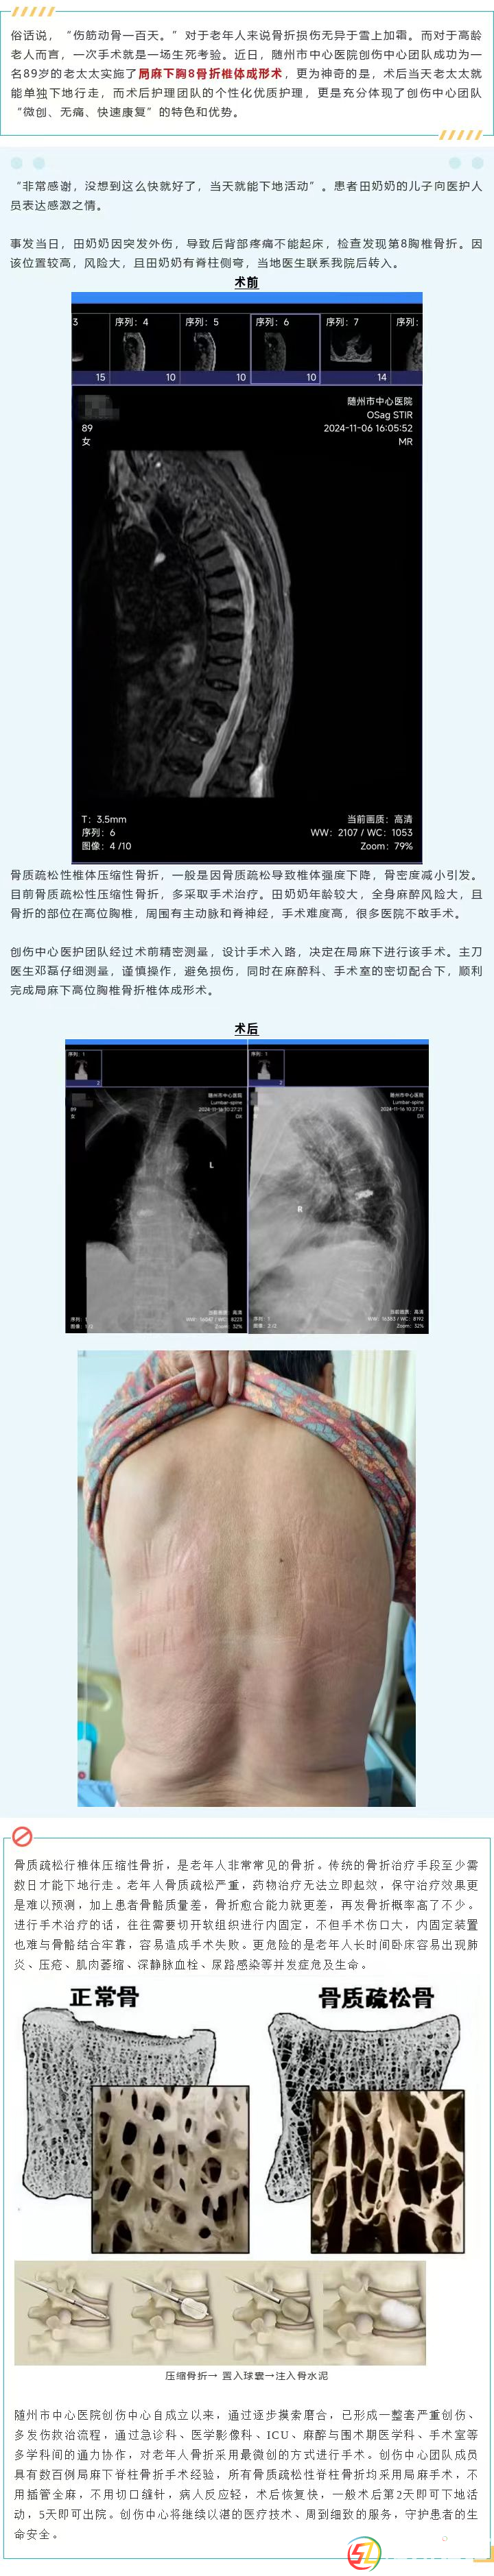

【微創(chuàng)技術(shù)】九旬老人胸椎骨折,術(shù)中局麻,當(dāng)天即下地行走!這是什么神操作?